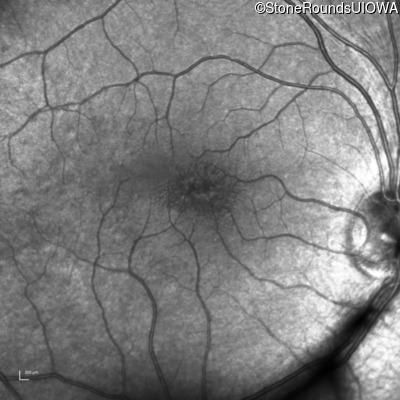

XL Retinoschisis (IIIB1)

Age at visit: 7 years

This 7 year old boy failed a vision screening test at his pediatrician 5 months ago.